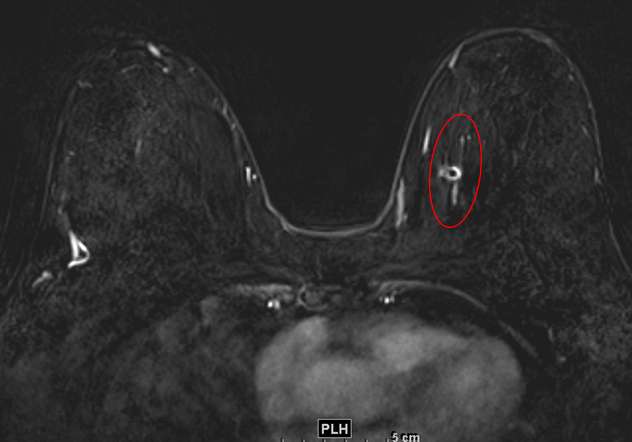

The combination of NME distribution and internal enhancement pattern with other morphologic MRI features and contrast kinetic curves (discussed separately) can help differentiate findings that are more or less suspicious for malignancy, but often NME findings ultimately require MRI-guided core needle biopsy for definitive diagnosis.4 Figures 1 through 3 demonstrate examples of biopsy-proven malignant NME.